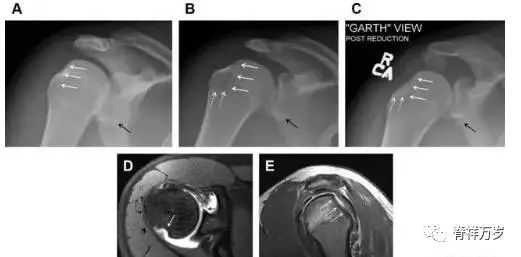

骨折伴盂肱关节不稳

肩关节是最容易脱位的关节之一,肩关节脱位常伴随其它结构的损伤,如血管神经损伤、肩袖损伤、盂唇损伤、Bankart 损伤等。脱位本身诊断往往是明确的,容易被忽略的是其继发的伴随损伤。

需要仔细评估肱骨头、大结节、关节盂边缘、肩峰、喙突等结构。典型的 X 线投射角度包括:内旋位前后位片、外旋位前后位片(Grashey 位)、侧位(肩胛骨 Y 位)、腋位片以及改良腋位片。

图 6 肩关节前脱位伴有 Hill–Sachs 和 Bankart 损伤:(A~C)肱骨头后外侧撞击骨折,白色箭头所示为骨折的内侧边界;(A)内旋位前后位片,(B)「V」形压缩骨折的下边界(虚线短箭头),(C)Garth 位(轴向投影)示 Hill–Sachs 损伤(虚线和实线折箭头),特别是对骨性 Bankart 损伤的诊断有帮助。(D、E)MRI 进一步证实了损伤。